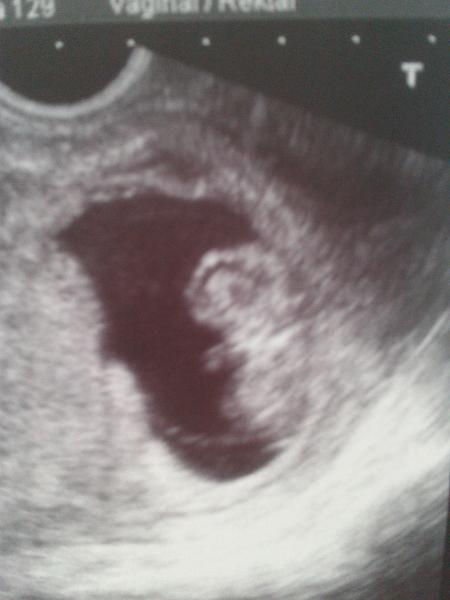

Mam sa super kocky, dakujem za opytanie 🙂 uz mi nebyva zle od zaludka takmer vobec. Skor ma chytaju take mdloby a ked mi je blbo, tak mi je na odpadnutie...uplne sa zmenili tie "nevolnosti" , ale mam taky pocit, ze sa tak u mna prejavuje hlad. Ked sa najem, tak mi to prejde. Ale nepocitujem hlad tak, ako netehotny clovek, ze citim, ze som hladna...ale zacne sa mi tocit hlava je mi tak tazko vseobecne a uklada ma na spanok...a klasicky hlad vobec necitim..dokonca mam pocit, ze by som do seba nic nedostala...a ked zacnem jest, tak to nema konca kraja 😀 😀 😀 jem straaasne vela 🙂 ale bola som vykupit bioobchod a nakupila som si tam dobrotky a keksiky a take zdrave maskrty, co mam po ruke a ked som hladna, tak zobkam 🙂 ale uz nevraciam, tak som rada 🙂 Posielam vam aj fotku nasej pretransformovanej krevetky na cloviecika 🙂

jeeeej miuskaaaa ved to uz je babo !! a nie plod 😉

@11miuska11 jeeeej to je ale krasny obraztek 😎

@11miuska11 Miuska to je krasne bejbatko 😵 😵 😵 Bozinku keby tak kazdy kto po takom tuzi aj mohol mat.....

@11miuska11 jeej krásny malinkýý juuj to musi byt superajja chceeemm